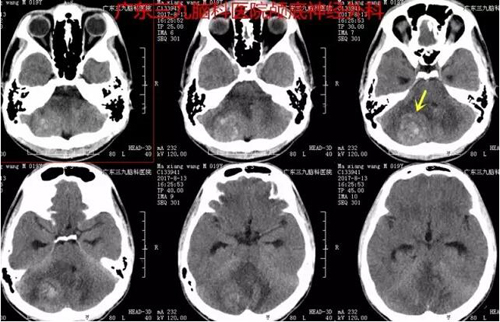

马某,男,19岁,因“头痛10天,加重伴行走不稳2天”于2017年8月9日入院,影像检查示右侧小脑角占位,完善相关检查后在全麻下行全脑血管造影+右侧小脑肿瘤栓塞术,术后立即送手术室,由神经外一科张良主任主刀,行“右侧小脑血管母细胞瘤切除术”,术程顺利,术中病变全切除,术后病理报告示:动静脉畸形。

图1:术前CT提示右侧小脑团块状稍高密度为主占位性病变,间杂多发点片状高密度影,边界显示欠清,范围约3.4cm×3.3cm,周围示大片状低密度水肿影,四脑室受压变窄